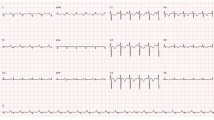

A 7-year-old boy was hospitalized in November 2009 because of rash and fever after receiving a shot of AdimFlu-S (A/H1N1) vaccine. About 1 month later, he died. Figure 1 illustrates the whole course of disease and therapy. The boy had traveled to Malaysia and had contact with chameleons, peacocks, mice, and turtles 1 month prior. In the late course of disease, total blood count showed RBC 2.72 × 106/μL, WBC 32,920/μL, and platelets 52,000/μL. The coagulation screen was abnormal, with prothrombin time (PT) 15 s and partial thromboplastin time (PTT) 68.1 s. The liver function tests were abnormal, with total serum bilirubin 2.25 mg/dl, glutamate oxaloacetate transaminase (GOT) 736 U/L, and glutamate pyruvate transaminase (GPT) 137 U/L. There was diffuse intravascular coagulation (DIC), with D-Dimer > 35 μg/ml, fibrinogen > 0.035 mg/dl, and fibrin degradation products (FDP) 468.4 μg/mL. Serum showed high levels of triglycerides, lactic dehydrogenase, and ferritin at 178 mg/dl, 9560 U/I, and 142,874 ng/ml, respectively.

An 11-month-old female infant with respiratory symptoms for 1 week was admitted to the pediatric clinic in October 2012. She was diagnosed with an upper respiratory tract infection and received a shot of MF59-adjuvanted influenza vaccine 9 days later. The following day, she was admitted to the hospital because of vomiting and dyspnea and had an episode of seizure on the way to the hospital. She was in cardiac arrest upon arrival to the emergency department and died despite vigorous resuscitation. Blood samples obtained right after the start of cardiopulmonary resuscitation showed a leukocyte count of 12,200 cells/mm3, with a lymphocyte proportion of 60% and a neutrophil proportion of 35%. Her platelet count was 336,000/mm3. The hemoglobin level was 8.13 mg/dl with a mean corpuscular volume of 68.8 femtoliters. The level of C-reactive protein was 0.09 mg/dl, and the alanine transaminase and aspartate transaminase levels were 12 and 36 IU/ml, respectively. The creatine kinase and creatine kinase MB levels were 69 and 24 IU/L, respectively. The troponin I level was 0.13 ng/mL.